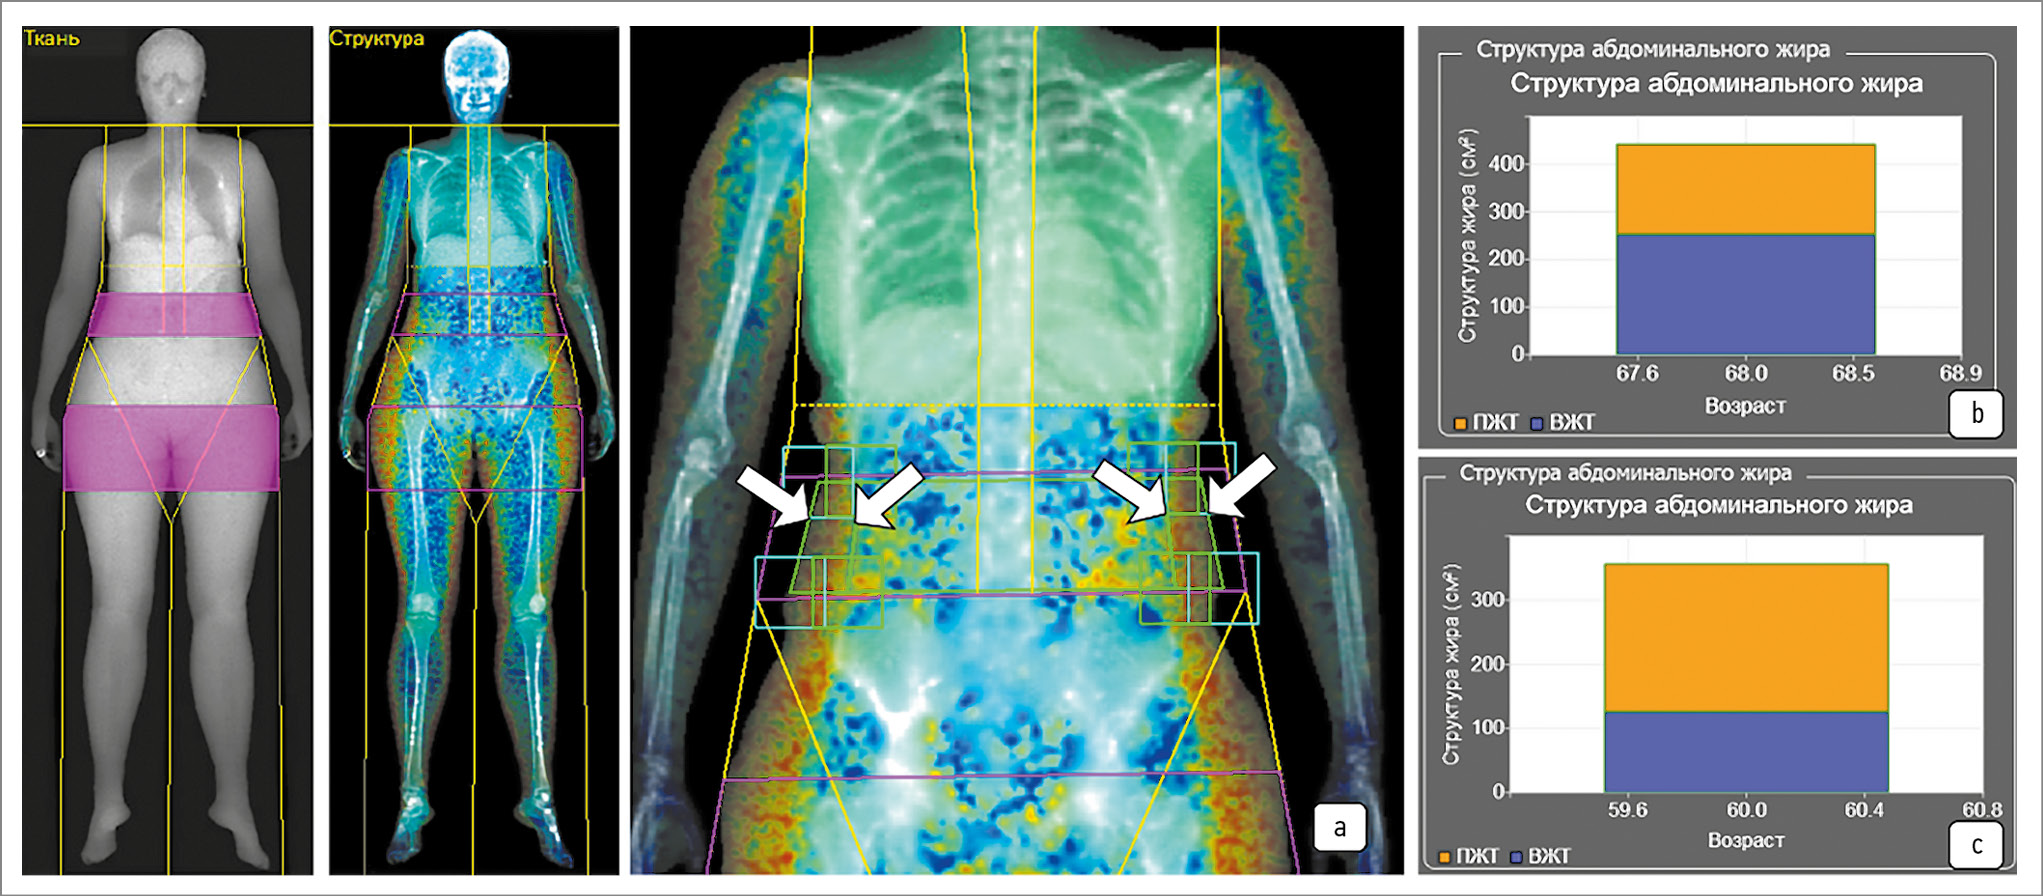

Рис. 5. Оценка структуры абдоминального жира при ДРА в режиме «Все тело»:

а – стрелками указаны корректные трапециевидные боксы (зеленого цвета) ручной разметки ПЖТ; b – структура абдоминального жира (см2) с преобладанием ВЖТ; c – структура абдоминального жира (см2) с преобладанием ПЖТ.

Методика ручной разметки жировой ткани после автоматического оконтуривания для корректного расчета структуры абдоминального жира при выполнении ДРА в режиме «Все тело» принципиальна для получения более точных результатов и представлена на рис. 5.

Толщина висцеральной жировой ткани (мм), оцененная при использовании ДРА в режиме «Все тело», имеет прямую пропорциональную связь со степенью стеатоза печени по данным количественной ультразвуковой стеатометрии.

Так, доля ВЖТ увеличивается с ростом ИМЖ, преимущественно у пациентов мужского пола, исключение составили женщины в возрасте старше 42 лет.

Итого из 549 (100%) пациентов со стеатозом печени по данным методов визуализации (в том числе качественной оценки) у 504 (91,8%) количественно подтвердилось наличие стеатоза печени, из них у 465 (84,7%) пациентов обнаружены избыточная масса жира или ожирение (67%). У 298 (54,2%) пациентов площадь ВЖТ превышала ПЖТ, что позволяет отнести этих пациентов в группу высокого риска развития осложнения коморбидной патологии.